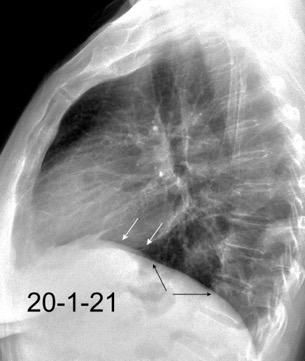

Parálisis frénica transitoria tras cirugía de válvula aórtica

Parálisis frénica transitoria post cirugía cardiaca (10%).

Puede acompañarse de atelectasia del LII.

Benjamin JJ et al. . Left lower lobe atelectasis and consolidation following cardiac surgery: the effect of topical cooling on the phrenic nerve. Radiology 1982